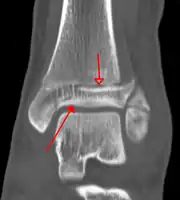

A triplane fracture of the ankle as seen on plain X-ray

A triplane fracture of the ankle as seen on CT